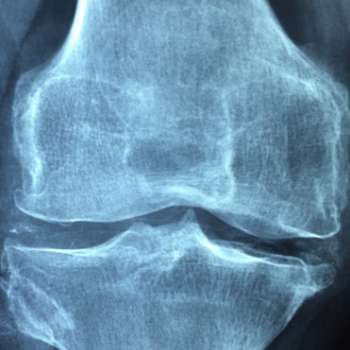

골다공증 증상6. 관절 통증 및 강직

골다공증이 진행되면서 관절 주변의 뼈와 연골도 약해질 수 있습니다. 이는 관절 통증과 강직을 초래하며, 특히 아침에 일어날 때나 장시간 앉아 있다가 일어날 때 증상이 더 심해질 수 있습니다. 이러한 증상은 일상적인 움직임과 활동을 방해하고, 환자의 이동성을 제한합니다. 관절 통증은 특히 무릎, 엉덩이, 손목 등의 부위에서 흔히 발생하며, 이는 환자의 생활의 질을 저하시킬 수 있습니다.